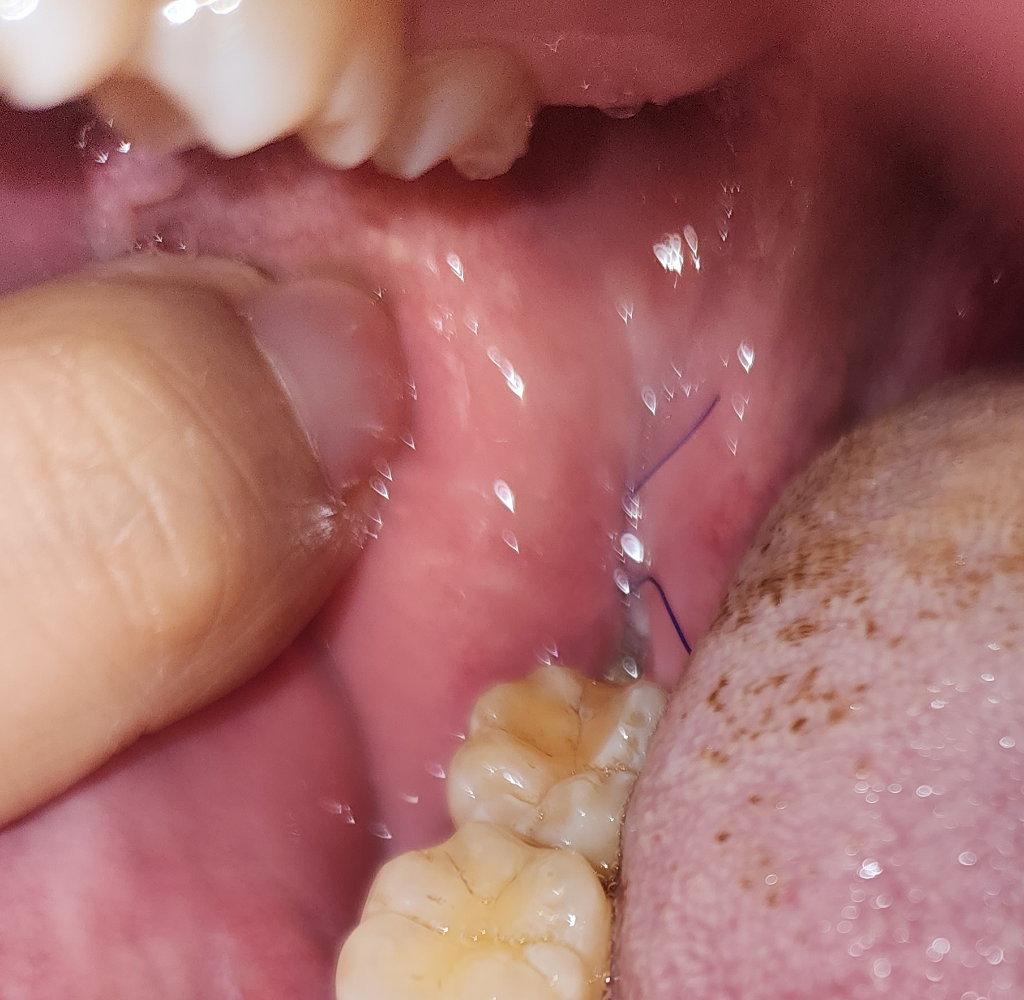

대학병원에서 매복사랑니 포함 4개를 동시 발치 후 9일차입니다.(아랫니 2개만 매복, 윗니 정상)

한 5일차까지는 통증이 별로 없었는데, 6~7일차부터 우측 한쪽만 통증이 점점 심해지는 느낌입니다.

턱아래 부분과 광대쪽에 통증이 느껴지고 두통도 함께 있는것 같습니다.

실밥은 4일후 뽑으러 가는데 그전에 동네 병원이라도 가보는게 나을지 궁금하네요.. 시기상으로 드라이소켓은 아닌것 같고 음식물등으로 인한 신경쪽 염증이 아닌가 걱정이 되네요.

(안아픈쪽과 다르게 구멍이 보이고 그안에 하얗고 검은것들이 보입니다..)

사진상으로는 크게 이상이 있어 보이지는 않기에 우선 소염진통제를 구매하여 복용을 해보고 통증이 지속되는 경우에는 치과진료를 받길 권합니다.